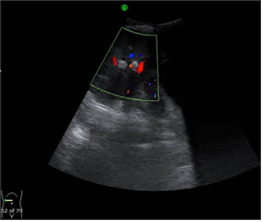

Los hallazgos más significativos de la ecografía abdominal al ingreso fueron (Fig. 1)(Fig.2): Textura hepática homogénea, vesícula dilatada que mide 100x40mm, pared 3,5mm, dilatación de más de 5mm en las vías biliares intrahepáticas con litiasis pequeñas en su interior, colédoco tortuoso, mide 14mm de diámetro con litiasis de 13x7mm en su interior, el resto de las vísceras abdominales sin alteraciones aparentes.

Otras características que pueden detectarse mediante ecografía incluyen cálculos biliares, abscesos hepáticos, "biloma" y colangiocarcinoma. Se puede realizar una aspiración percutánea con aguja fina guiada por ecografía en caso de sospecha de tumor hepático. 11,12 En este caso, la primera investigación por imágenes realizada fue la ecografía de abdomen que muestra un cálculo alargado dentro del colédoco dilatado e imagen ecogénica dentro de las vías biliares intrahepáticas dilatadas y engrosamiento ecogénico adyacente a la pared de la vía biliar. Posteriormente se realizó una tomografía computarizada de abdomen con contraste, para definir la dilatación de la vía biliar que se aprecia mejor en un estudio contrastado, la constitución mixta de las litiasis, propias de los cálculos biliares y sirvió además para descartar otras complicaciones como formación de abscesos, cirrosis hepática, biloma o rotura de la vía biliar con peritonitis y colangiocarcinoma, como vimos la pancreatitis estaba presente como complicación. No se realizó colangiopancreato resonancia a este paciente porque fue remitido a institución terciaria para definir diagnostico y tratamiento, donde fue diagnosticado finalmente con la CPR por los hallazgos de litiasis biliares, estenosis fibrótica y dilatación de las vías biliares.